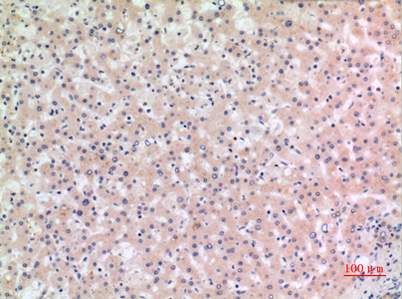

Dilutions: Western Blot: 1/500 - 1/2000. IHC-p: 1/100-1/300. ELISA: 1/20000. Not yet tested in other applications.